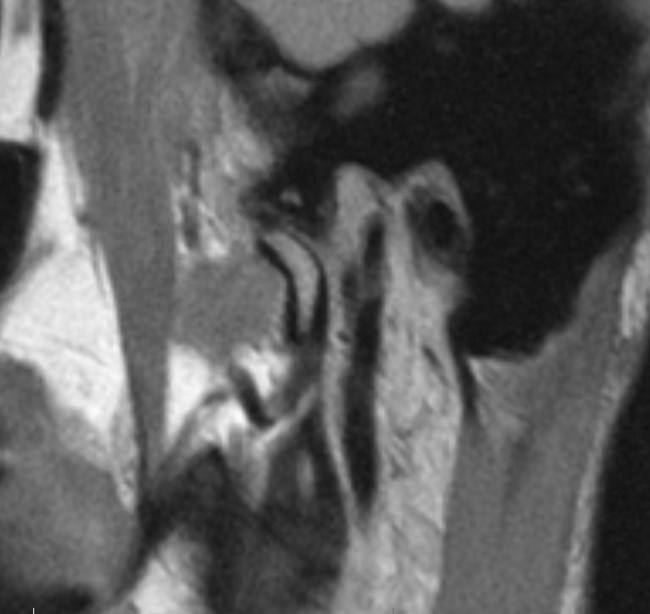

Na podstawie uzyskanych wyników badań zastosowano repozycyjną szynę zgryzową oraz terapię manualną narządu żucia. Po trzymiesięcznym leczeniu uzyskano poprawę modelu ruchomości żuchwy. W związku z utrzymywaniem się silnych dolegliwości bólowych zlecono dodatkowo badanie tomografii rezonansu magnetycznego (MR), w którym w zwarciu stwierdzono obustronne doprzednie przemieszczenie krążków stawowych (ryc. 5). W zwarciu na przekrojach czołowych widoczne było spłaszczenie powierzchni stawowej lewego ssż (ryc. 6). W rozwarciu pozycja obydwu głów żuchwy była doprzednia w stosunku do szczytów guzków stawowych, a nad głowami żuchwy leżały pasma przednie krążków stawowych. Przemieszczenie głowy żuchwy było bardziej nasilone w prawym stawie skroniowo-żuchwowym (ryc. 7).

Ryc. 7a i 7b. Przekroje strzałkowe MR ssż w rozwarciu, obrazy PD-zależne. Doprzednie położenie głów żuchwy w obydwu ssż, nad głowami żuchwy widoczne pasma przednie krążków stawowych.